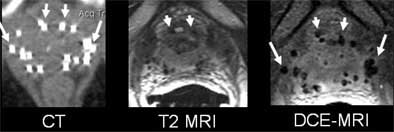

| Wayward brachytherapy seeds are well visualized, and better localized, in the contrast-enhanced MRI (the "D" in DCE-MRI stands for "dynamic," which is not necessary to optimize seed visualization, according to the authors). In patient 1 (top), a brachytherapy seed has migrated to the neurovascular bundle. In patient 2 (below), CE-MRI shows a seed that has lodged in a seminal vesicle, but cannot be localized in CT image at left. In patient 3 (bottom), the migration of seeds to the penile bulb is readily visualized on contrast-enhanced ("CE") MRI, lower right. All images courtesy of Dr. Klaus Kubin. |

According to the results, the T1-weighted GRE sequence localized 92% of the seeds overall (with per-patient accuracy ranging from 87%-99%), 14% of which were periprostatic. Twenty-five percent of the seeds were located in the neurovascular bundle, and 4% in the seminal vesicles.

T2-weighted MRI localized 78% of the seeds overall (range, 74%-86%), including 12% in periprostatic distribution, which was diagnosed more accurately on the T2 images. Twenty-four percent were found in the neurovascular bundle and 3% in the seminal vesicles, Kubin said.

CT won the sensitivity race, locating 97% of the seeds (range, 95%-100%). Two percent were suspected to be extraprostatic; however, the group was unable to assign the seeds to specific periprostatic structures.

The group concluded that T1- and T2-weighted MR were both more accurate for postbrachytherapy seed distribution than CT.

"The main idea is that the prostate takes up contrast media in general, not only the cancer, so if you wait long enough (up to 11 minutes after injecting contrast) the whole prostate is contrast enhanced," Bloch said. "But the seeds, of course, you see as voids because there is no contrast uptake. So if you use high-spatial-resolution MRI, no matter if it’s T2- or T1-weighted contrast enhanced, you see very nicely the prostate, the prostate capsule, and the neurovascular bundle, the penile bulb, and the rectal wall, but until now you couldn’t see the seeds."